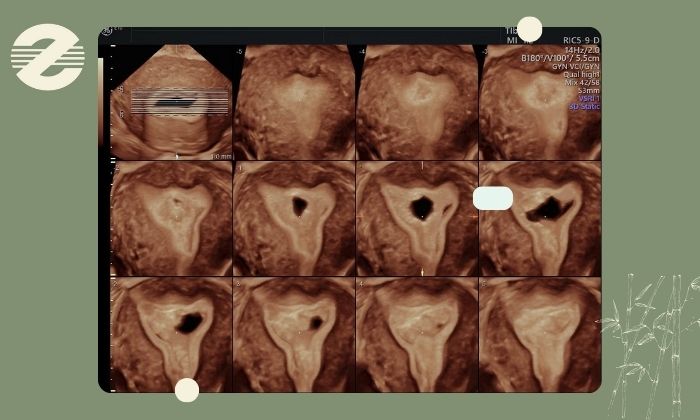

سونوگرافی سه‌بعدی رحم یکی از پیشرفته‌ترین روش‌های تصویربرداری در حوزه زنان و رادیولوژی است که با استفاده از تکنولوژی دیجیتال، تصاویر حجمی، دقیق و سه‌بعدی از رحم، تخمدان‌ها و ساختارهای اطراف آن ارائه می‌دهد. در حالی که سونوگرافی دو‌بعدی تنها برش‌های سطحی و مقطعی را نشان می‌دهد این روش امکان مشاهده ساختار کامل رحم از زوایای مختلف را فراهم می‌کند و دقت تشخیص را به‌طور قابل ‌توجهی افزایش می‌دهد.

از آنجایی که بسیاری از ناهنجاری‌های مادرزادی رحم مانند سپتوم (تیغه میانی)، رحم دولوبی، رحم تک‌شاخ، رحم دوگانه و مشکلات مربوط به گردن رحم یا واژن می‌توانند باعث ناباروری، سقط مکرر یا اختلالات قاعدگی شوند، سونوگرافی سه‌بعدی نقش مهمی در تشخیص آن‌ها دارد. این روش به متخصص اجازه می‌دهد ساختار و تقارن دیواره‌های رحم را با وضوح بالا بررسی کند و بر اساس اطلاعات دقیق به‌دست‌آمده تصمیم‌گیری درمانی و برنامه‌ریزی‌های مرتبط با باروری را با دقت بیشتری انجام دهد.

در سونوگرافی سه‌بعدی تصاویر با وضوح بالا تهیه می‌شود و متخصص می‌تواند شکل واقعی رحم، تقارن دیواره‌ها، وجود تیغه، انحرافات و ناهنجاری‌های مادرزادی را بدون خطا بررسی کند. این دقت بالا باعث کاهش تشخیص‌های اشتباه و انتخاب درمان مناسب‌تر می‌شود.